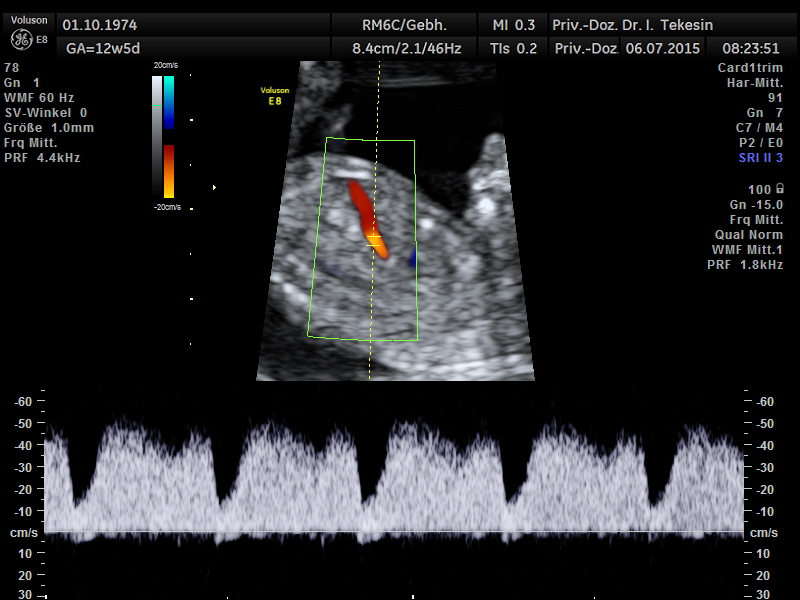

Fetale Zirkulation in der 13. SSW